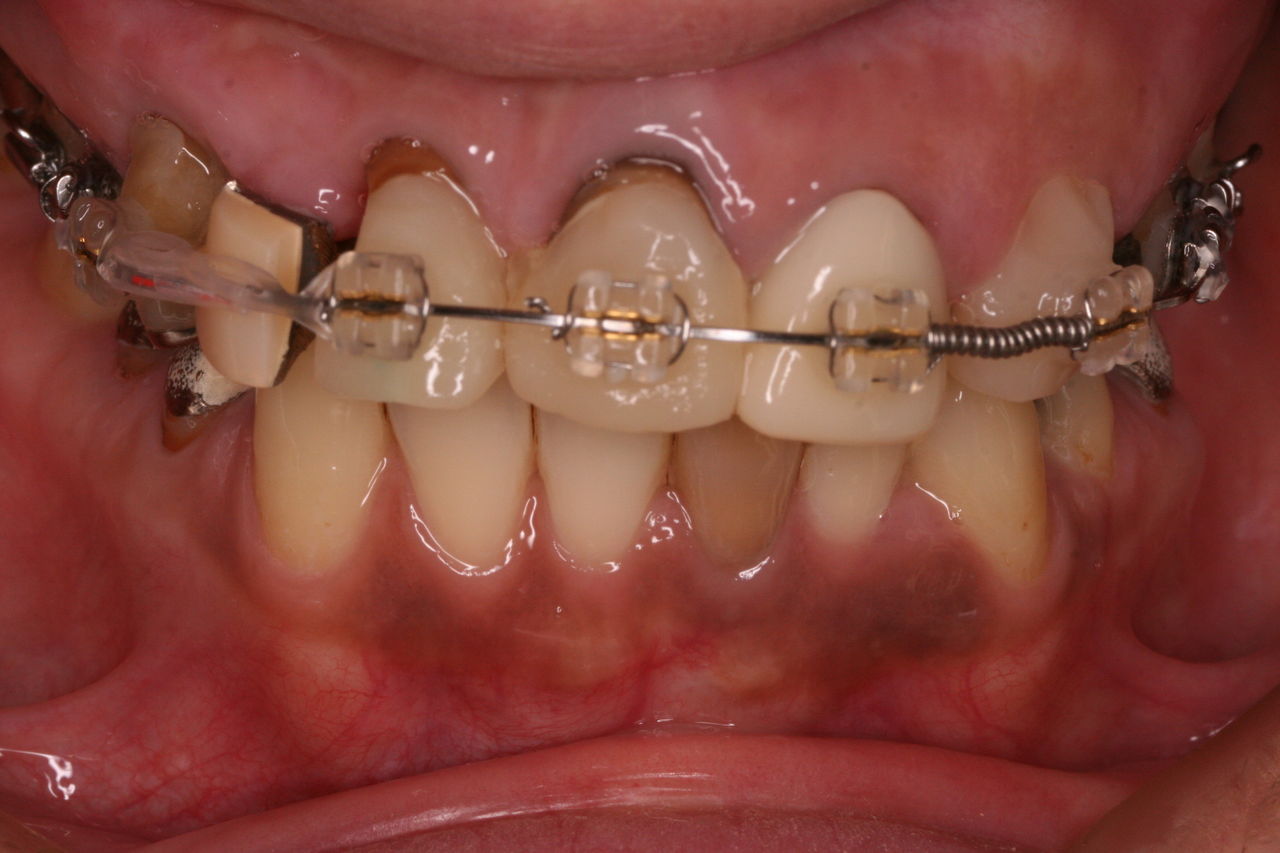

おそらく、数年前はきれいな差し歯が入っていたと推測されます。

正面からみると歯茎の黒ずみがきになります。原因は2つあり、ひとつは金属の土台から溶出される銀イオンです。もう1つは、歯を削るときにでる切削片が歯肉の中に入り込んでしまうのです。どちらも時間の経過とともに目立ってきますが、最近の審美治療ではこのようなことが生じません。

上から見ると、前歯はブリッジとなっており、左右1本づつ歯が欠損しております。

つまり、歯を抜いたのが左右1本ずつで、残りの歯をけずってブリッジにしております。